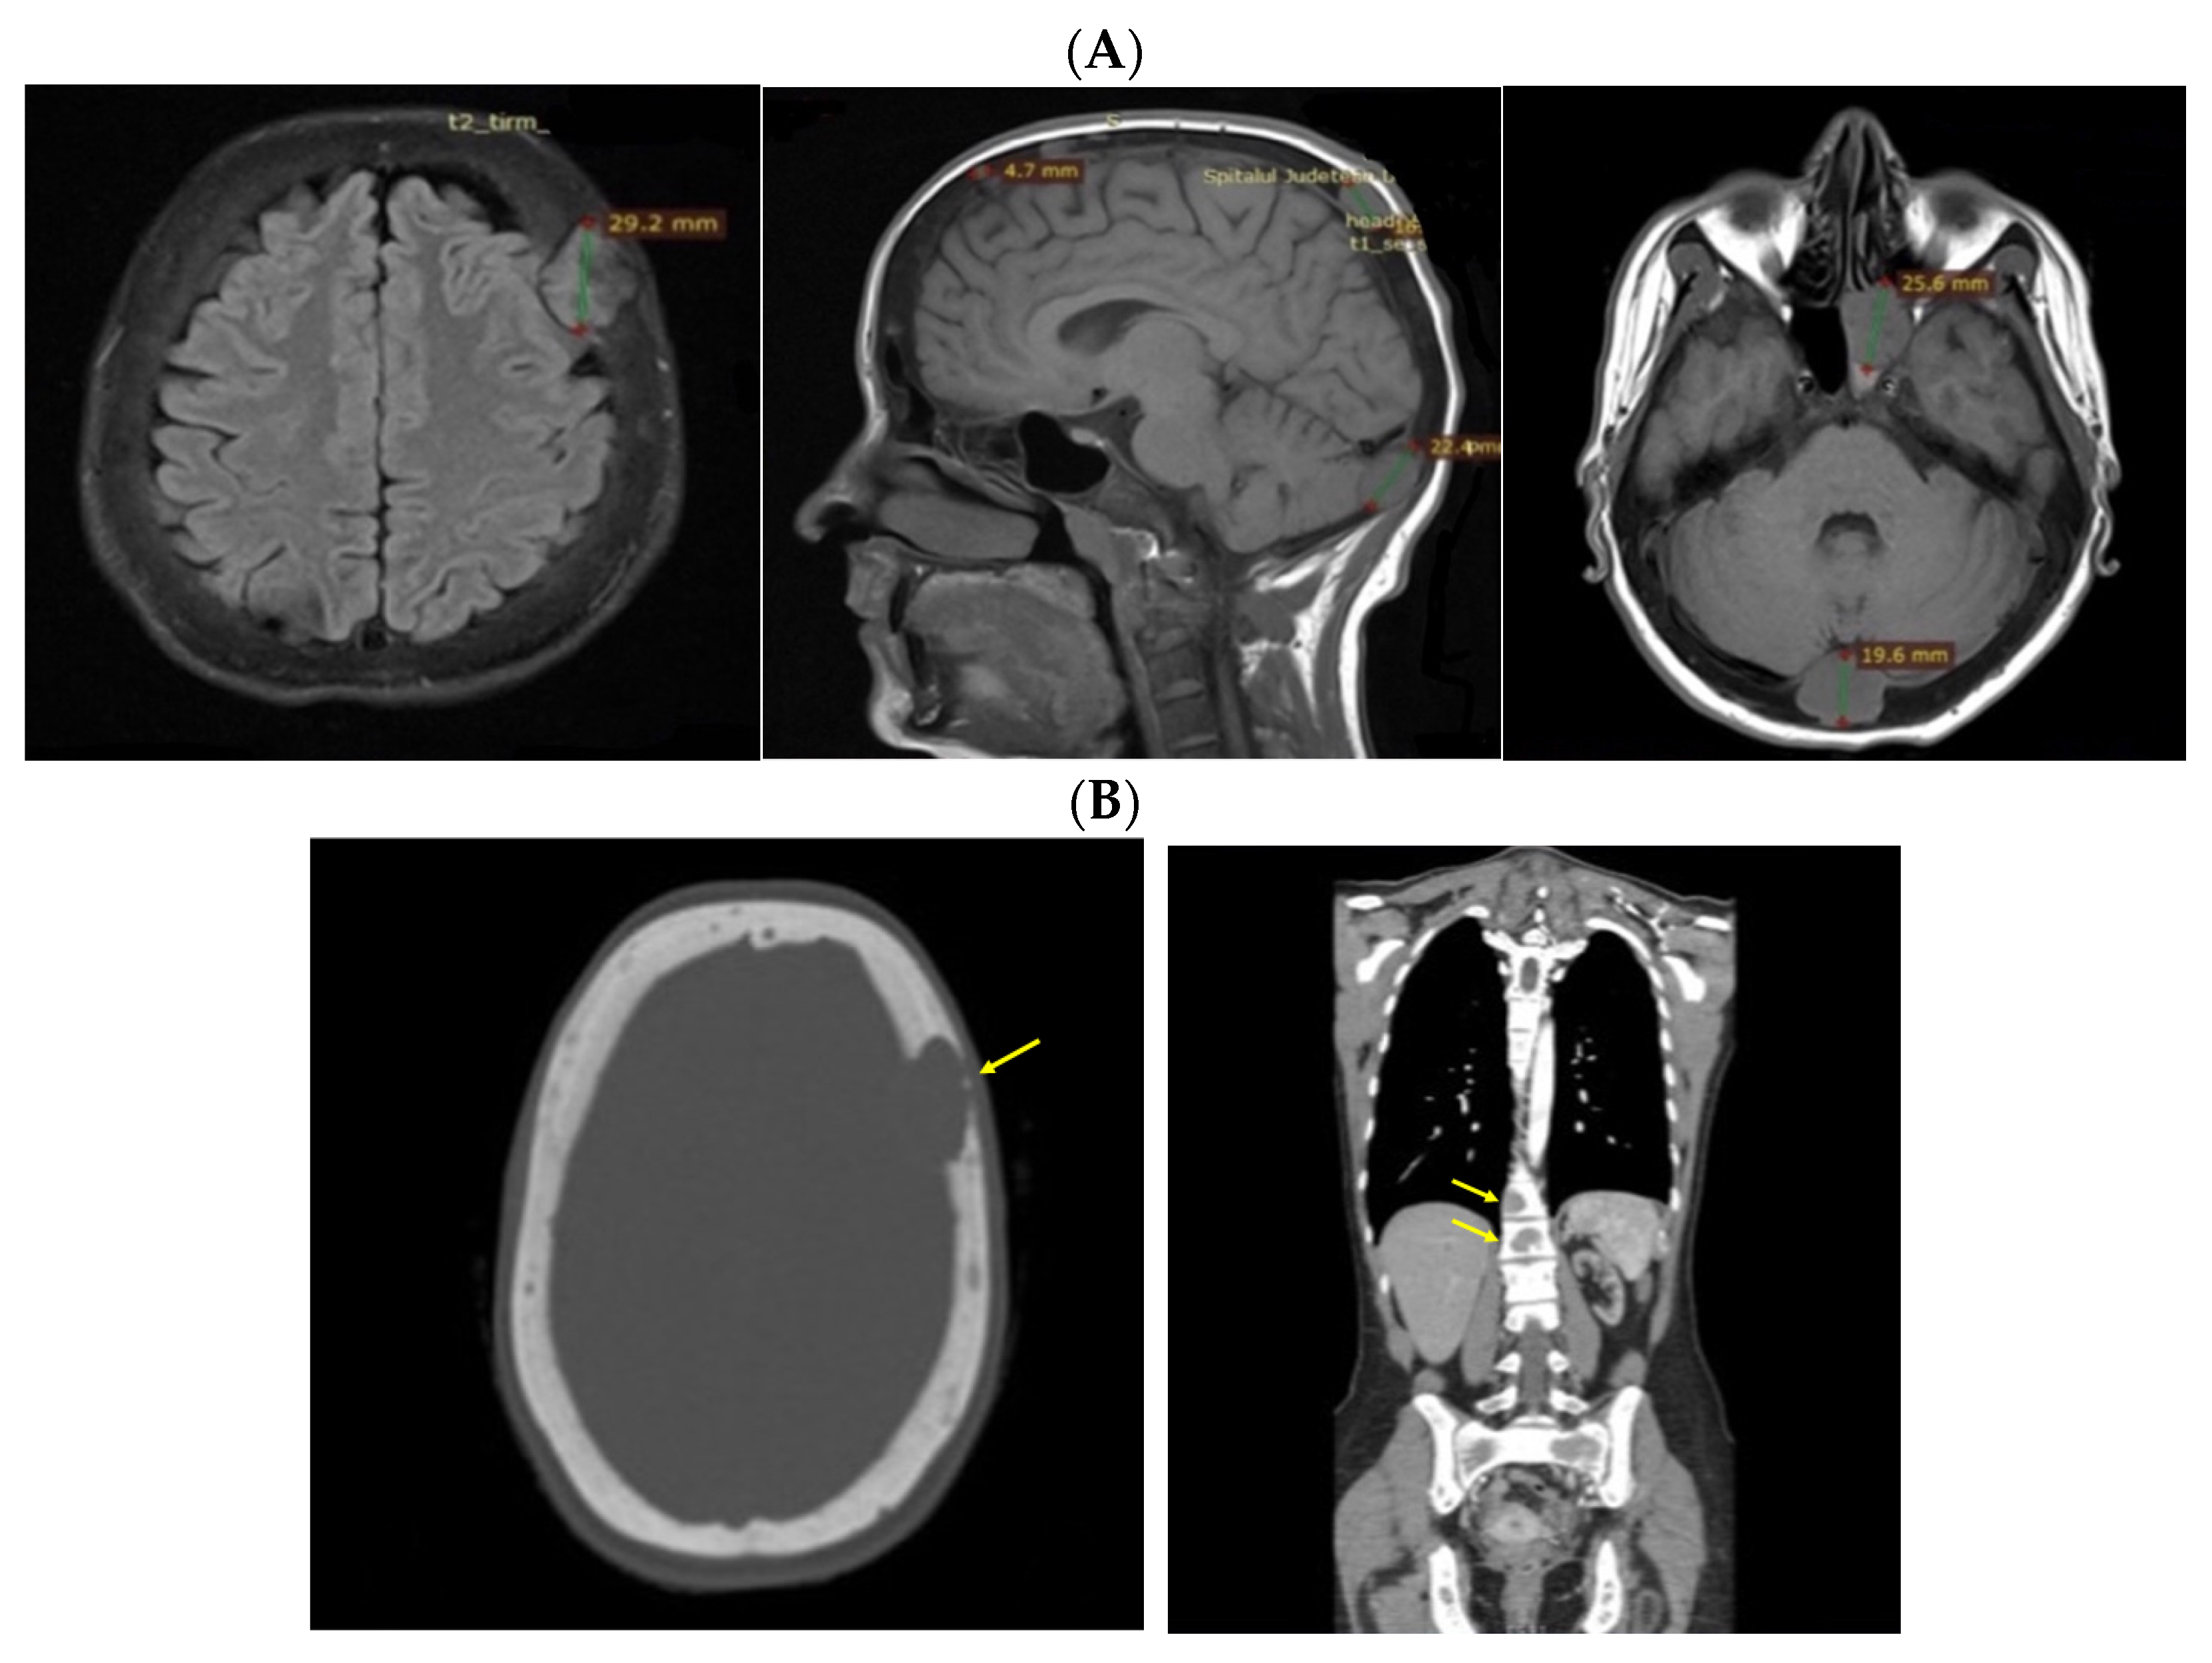

Despite recommendations, she proved poorly compliant once again, and she was re-admitted only seven months later when she suffered a spontaneous fracture at the second cervical vertebra that required immobilization with a cervical collar. Amid this novel hospitalization, the PTH levels remained high with a reduced alkaline phosphatase level (Table 4). A native spine CT revealed an odontoid fracture involving the C1 anterior arch, also confirmed with a native magnetic resonance imaging (MRI) evaluation. Moreover, other left intramaxillary bone lesions were discovered. In this context, the examinations were extended to the level of the skeleton, and the head-thorax-abdomen-pelvis CT scan with intravenous contrast revealed multiple lesions located at different levels, such as the skull (of 3.5 by 3.8 cm), sternum (of 2.9 cm), sacrum (of 4 by 5.5 cm), and pelvis (of 6.5 by 5.5 cm) (Figure 12).

Figure 12.

Brown tumors in an adult lady with poorly controlled renal hyperparathyroidism. (A) Native craniocerebral magnetic resonance imagery (the lesions are highlighted as well as their largest diameter). (B) Intravenous contrast computed tomography showing the mentioned lesions (yellow arrow) at the level of the skull (left) and spine (right).